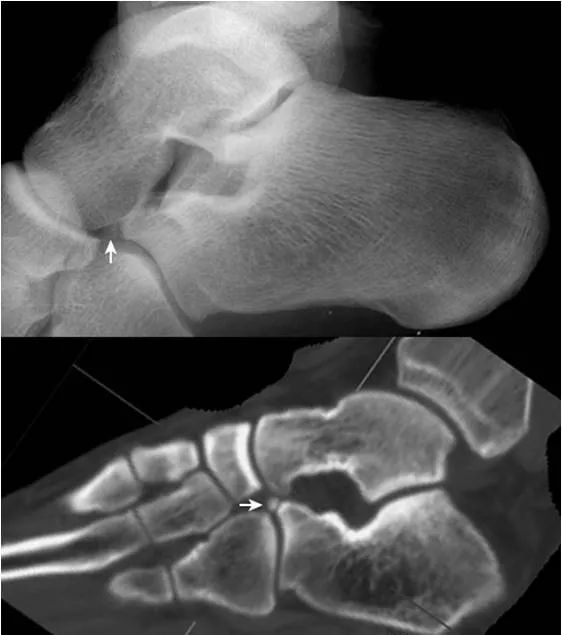

7.跟骨副骨:

位于距骨、跟骨、舟骨及骰骨所围成的间隙内,呈小的骨性突起(箭头),为正常变异。需与跟骨前缘的撕脱骨折鉴别。CT 矢状面重建图像清晰显示该副骨与各骨的关系。